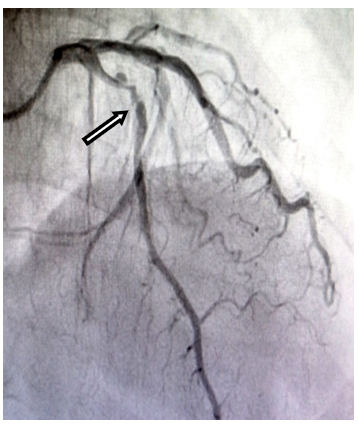

Subsequent coronary angiography showed 20% recanalisation of the proximal LAD obstruction (Figure. 3a, marked with arrow head). One drug-eluting stent (3.0 x 20.0 mm) was implanted across the lesion without complications (Figure. 3b, marked with arrow head). He was mobilized and discharged home in a stable condition. Echocardiogram at follow up two weeks later shows improvement of LVEF (50.6%).

Figure 3 (a): Patient’s coronary angiogram after thrombolysis.